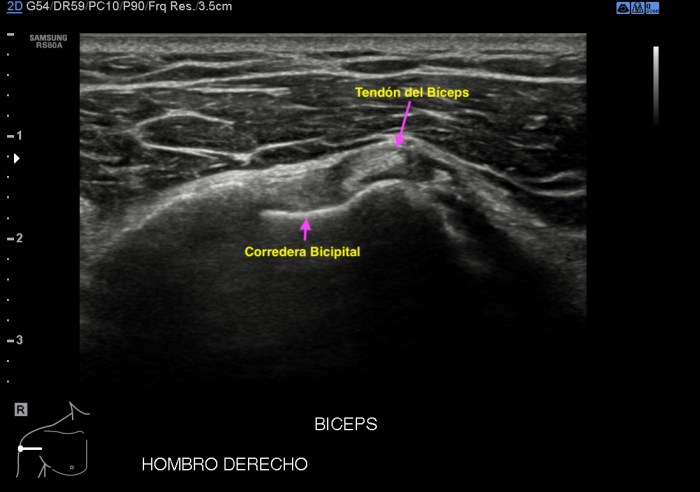

317. El tendón. Tipos y patología.

En Eco Msk uno de los objetivos principales de estudio es el tendón y su patología, lo primero es entender bien el tipo de tendón que vamos a estudiar, para posteriormente comprender bien que le está pasando y por la razón que puede estar sufriendo y es que no es igual un tendón de anclaje o de deslizamiento. Me explico:

Luxación e inestabilidad:

• Los tendones se mantienen en su posición por retináculos, poleas o retináculos especiales y los ligamentos.

• Esta patología requiere un estudio en eje corte y estudio dinámico.

• Bíceps, Perneos, Flexores y Extensores son los más habituales que sufran este tipo de patología.